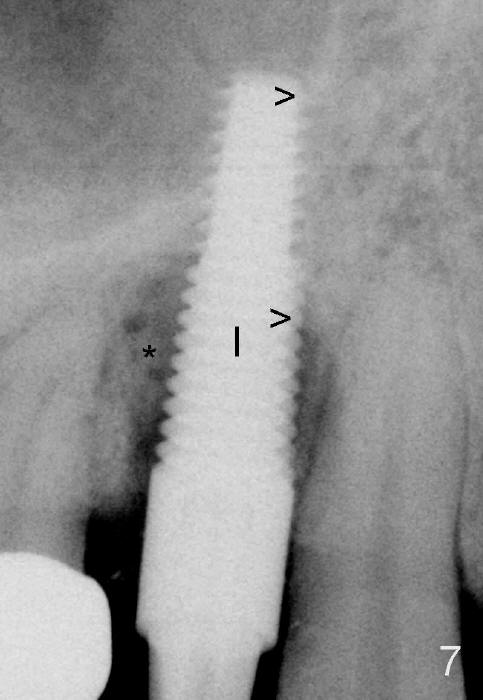

In spite of large periapical radiolucency (Fig.1 *), osteotomy is easier than expected. Use 2 mm pilot drill, 2.5-3.5 mm reamers from 14 mm (bottom of the socket) to 17 mm (sinus floor). The initial point for osteotomy at the bottom of the socket is easy to establish, because it is flat. By the time 5x20 mm tap is inserted, it is palatal (Fig.5). It is mandatory because the buccal plate has been perforated. The tap has to be inserted deeper (from 17 mm to 20 mm, Fig.6) to achieve stability. Insertion torque of 5x20 mm implant (Fig.7 I) is > 60 Ncm. The implant remains palatal so that there is space for bone graft (Fig.8 *). But the bone graft is a little over packed; there is no room to place collagen dressing. The latter will be dislodged and bone graft will be lost if perio dressing is loose prematurely. The perio dressing may have to be re-applied. Depth of bone graft is deemed sufficient if the implant threads are covered. Maximum will be on the rough surface. Physiologically, bone does not extend to the gingival margin.

As expected, the collagen dressing is dislodged when the perio dressing is off; fortunately the bone graft remains in place 7 days postop (Fig.9 *). To keep the bone graft in place, an immediate provisional (Fig.10 P) is fabricated and cemented; its margin (*) covers the graft. There is no occlusal contact in centric and lateral excursion. The patient is asked not to use this crown for 3 months.